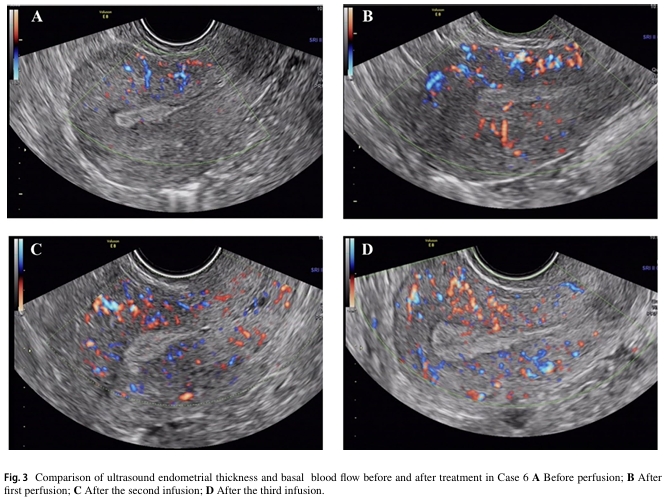

七名患者在术后进行三次自体骨髓间充质干细胞宫腔灌注治疗。两年内进行随访,子宫内膜厚度和基底层血流量均有明显改善,宫腔内形态正常,且均未检查到新的宫腔粘连症状。其中两例患者在术后分别经自然受孕和胚胎移植成功分娩。